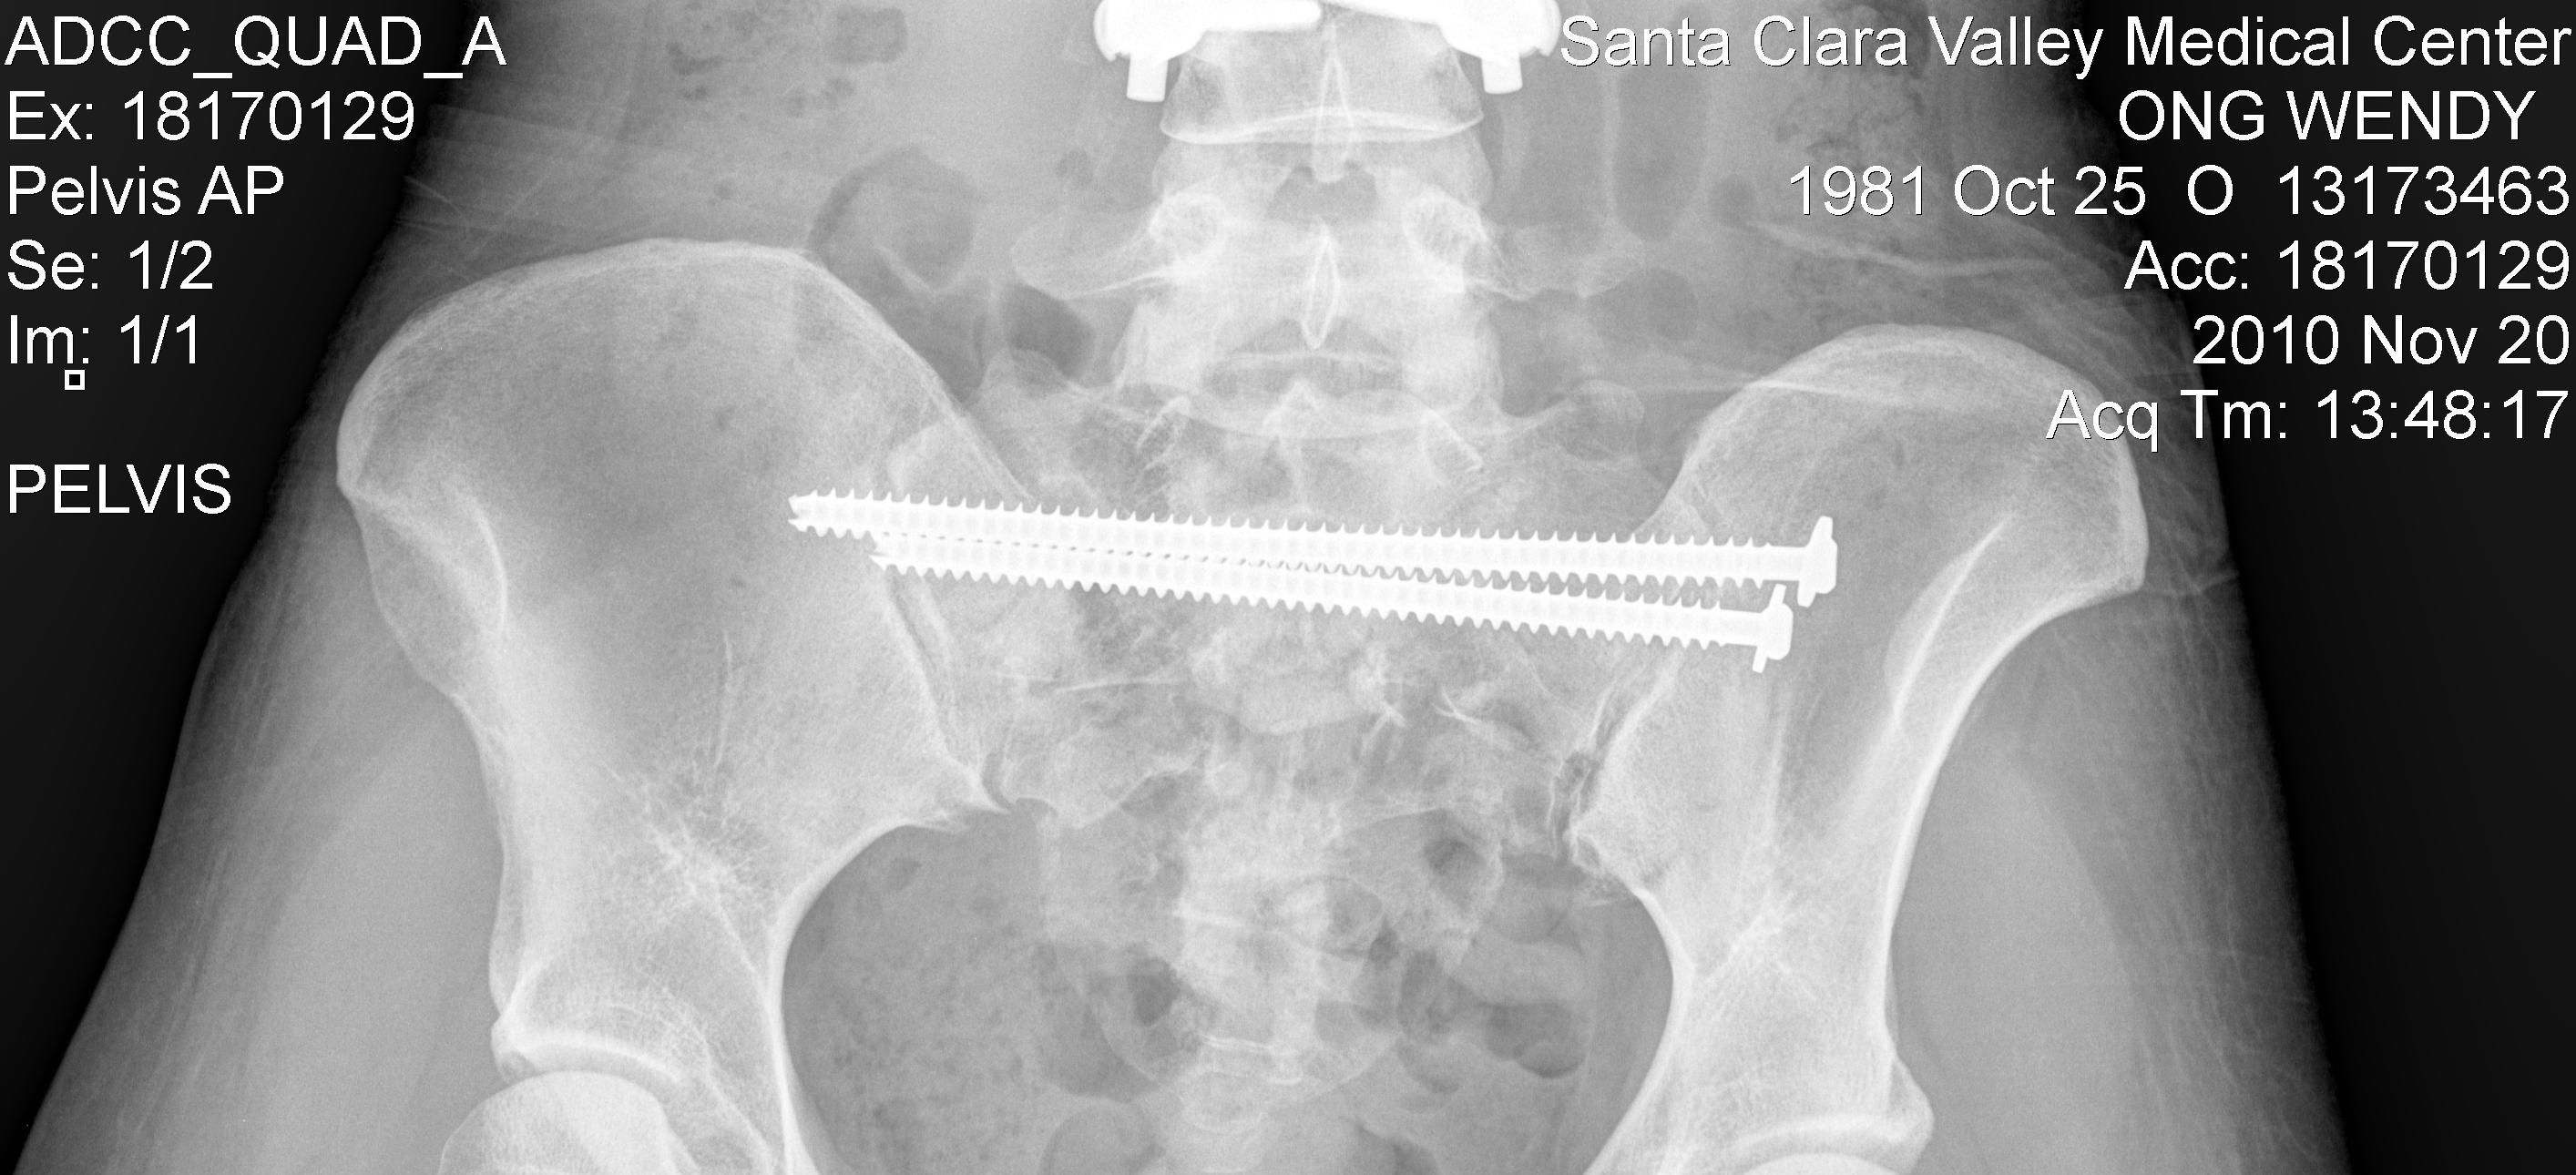

In October 2010, while sport-climbing at Owens River Gorge near Bishop, CA, I was dropped and fell close to 200 feet (70m), smashing to the ground. The result was a T-10 incomplete Spinal Cord Injury, Cauda Equina Syndrome (basically all the nerves at the base of my Spinal Cord/Sacrum were shredded up), shattered pelvis, disintegrated sacrum, exploded L-vertebrae, a paralyzed left-leg and a lifetime of chronic pain and impaired bowel/bladder function.

Aside from the vertebral fractures and Spinal Cord damage, my L2 vertebra exploded upon impact, my pelvis broke in multiple places and my sacrum was reduced to a collection of pebbles. The process of piecing back together humpty-dumpty was a long, arduous and very painful one.